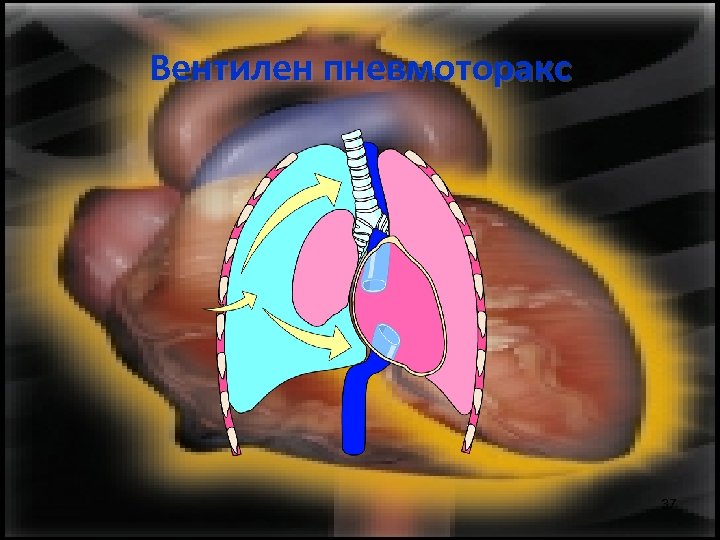

Вентилен пневмоторакс Основното в патогенезата му е, че поради изместването на медиастинума се прегъват съдовете, които постъпват в сърцето и навлизането на кръв в сърцето е преустановено. 35

Вентилен пневмоторакс 37

Вентилен пневмоторакс 38